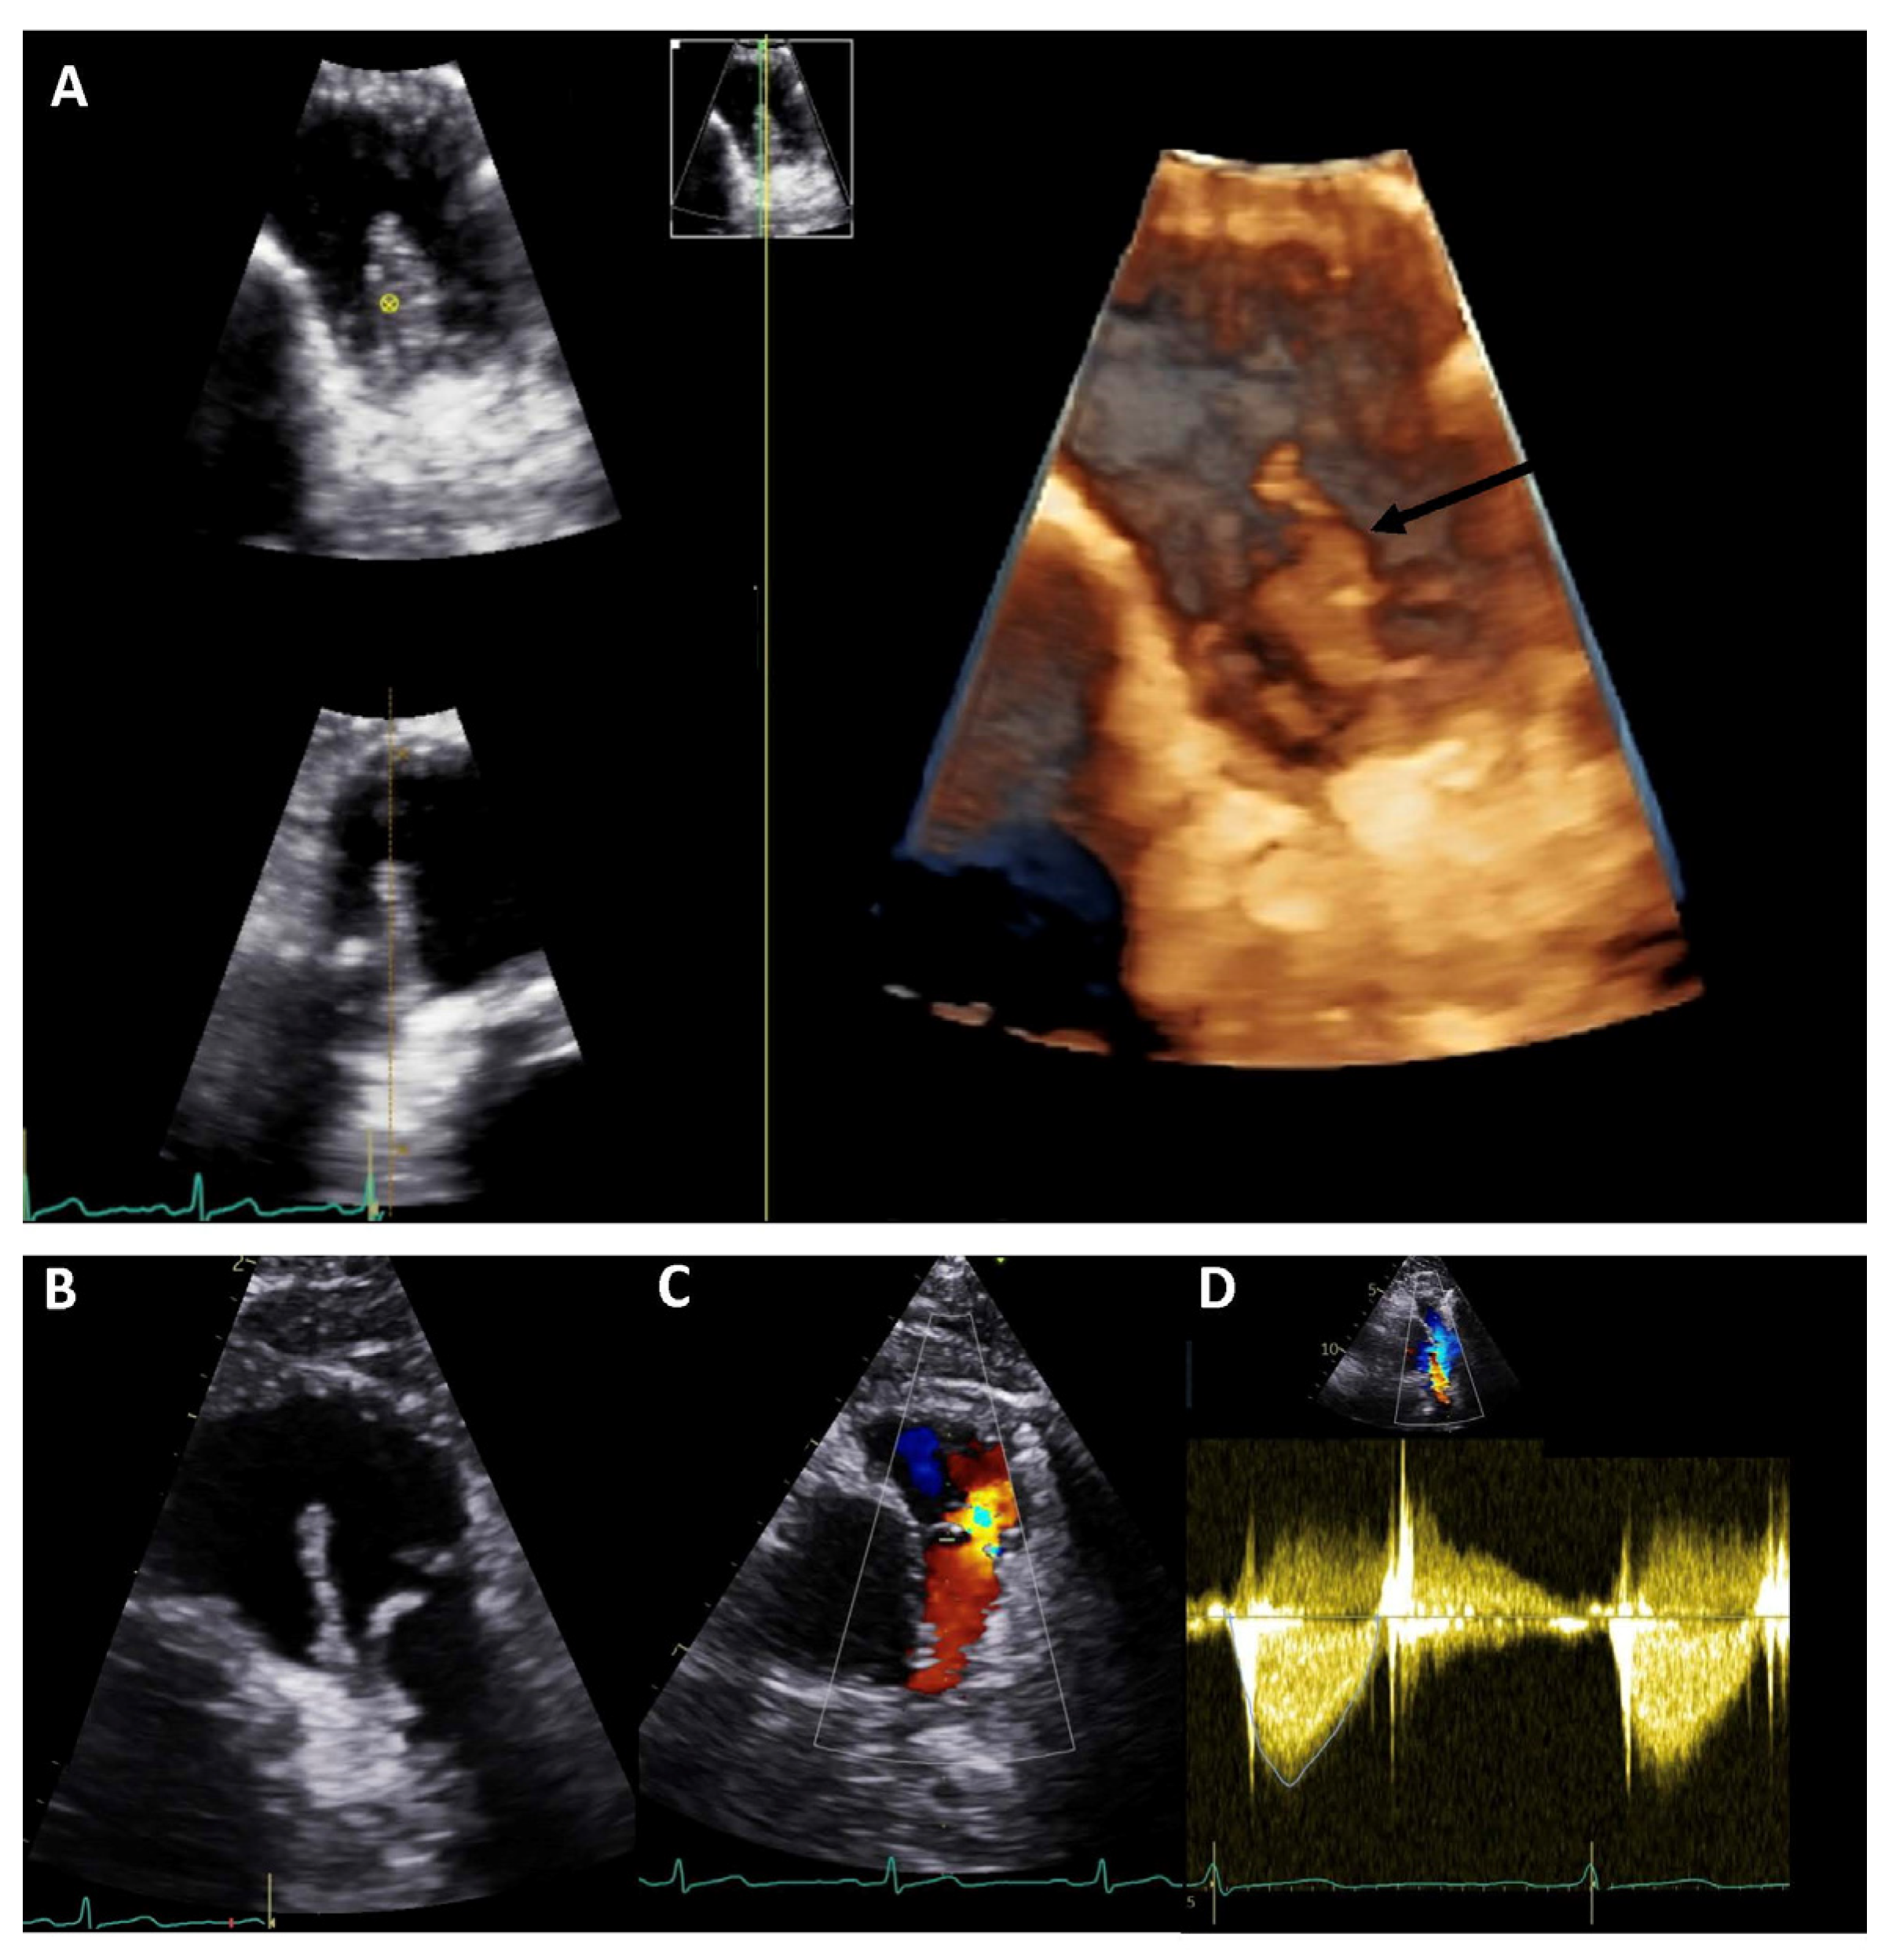

Figure 3. Cardiac computed tomography infective endocarditis visualisation. The images show right-ventricular pulmonary artery (RV-PA) conduit involvement (panels (A,B)) and systemic to pulmonary shunt involvement with a calcified lesion (panel (C,D)). The arrows indicate the vegetations.